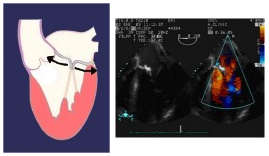

Un’ insufficienza mitralica di tipo II (prolasso dei lembi o lembi ipermobili) è causata da allungamento o rottura delle corde tendinee o da allungamento o rottura dei muscoli papillari in conseguenza, ad esempio, di un infarto miocardico acuto.

Insufficienza mitralica di tipo II, dovuta a rottura o stiramento di una corda tendinea (a sinistra e al centro), o a rottura di un muscolo papillare (a destra).